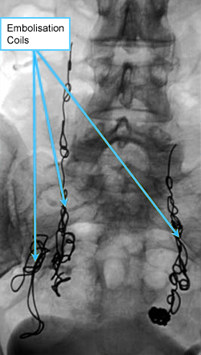

By using x-ray guided venography, planned by the results of the transvaginal duplex ultrasound, we are able to place very thin catheters directly into the veins that need treatment. Once the catheter is in place, a combination of foam sclerotherapy and insertion of a specialist inert metal coil can be placed into the vein, closing it and stopping the pelvic vein reflux.

Although some patients are concerned about having coils placed into their pelvic veins, the actual metal involved is less than the clips used in many surgical procedures such as laparoscopic hernia repair or laparoscopic gallbladder removal and far far less than the metal used in a hip replacement or other joint replacement procedure.